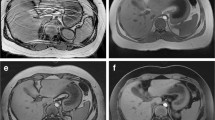

Representative images for free-breathing and breath-held abdomen exams are shown in Fig. 3. Abdomen scores for T1-W and T2-W imaging are shown in Fig. 4. For the T2-W sequences, there was no significant difference in the overall imaging scores (T2-W SSFSE mean 3.7 compared with radial T2-W mean 3.9, P=0.66). For the individual landmarks, the adrenal gland was the only structure that was significantly better visualized on the radial T2-W sequences (P<0.01). For the contrast-enhanced T1-W sequences, although there was no significant difference in the overall imaging scores between the two cohorts, or among the individual anatomical landmarks, the pancreas was better visualized on the T1-W mDixon than the 3-D radial (P=0.03).

Abdomen imaging examples and their scores. a Free-breathing axial radial T2-W MRI with fat saturation performed with intravenous sedation in a 24-month-old boy shows a dilated intrahepatic duct (arrow). The overall imaging score for the T2 sequence was 4.6. b Breath-held axial T2-W single-shot fast spin-echo (SSFSE) MRI performed with general anesthesia in a 29-month-old boy with lipoblastoma and retroperitoneal and subcapsular hepatic metastases (M). The imaging score for the T2 sequence was 3.8. c Axial contrast-enhanced T1-W 3-D radial MRI performed with intravenous sedation in same infant as (a), with an imaging score of 4.6. d Breath-hold axial T1-W modified Dixon performed with general anesthesia in same infant as (b), with an imaging score of 4.2

Artifacts encountered were low in incidence for both cohorts (mean motion artifact score was greater than 3.8 for both cohorts) with significantly increased motion artifacts encountered on the abdomen T2-W radial sequences (T2-W SSFSE mean of 4.7 compared with T2-W radial mean of 4.0, P<0.001).